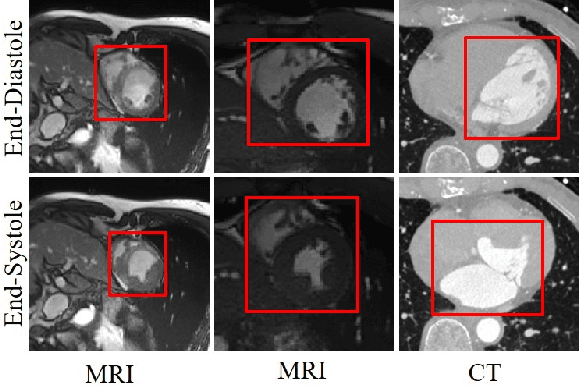

Dynamic medical imaging is usually limited in application due to the large radiation doses and longer image scanning and reconstruction times. Existing methods attempt to reduce the dynamic sequence by interpolating the volumes between the acquired image volumes. However, these methods are limited to either 2D images and/or are unable to support large variations in the motion between the image volume sequences. In this paper, we present a spatiotemporal volumetric interpolation network (SVIN) designed for 4D dynamic medical images. SVIN introduces dual networks: first is the spatiotemporal motion network that leverages the 3D convolutional neural network (CNN) for unsupervised parametric volumetric registration to derive spatiotemporal motion field from two-image volumes; the second is the sequential volumetric interpolation network, which uses the derived motion field to interpolate image volumes, together with a new regression-based module to characterize the periodic motion cycles in functional organ structures. We also introduce an adaptive multi-scale architecture to capture the volumetric large anatomy motions. Experimental results demonstrated that our SVIN outperformed state-of-the-art temporal medical interpolation methods and natural video interpolation methods that have been extended to support volumetric images. Our ablation study further exemplified that our motion network was able to better represent the large functional motion compared with the state-of-the-art unsupervised medical registration methods.